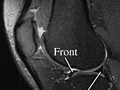

Resonancia magnética de la rodilla

Normales:

• Los ligamentos, meniscos, tendones, huesos y articulaciones tienen un tamaño, forma y ubicación normales.

• No hay crecimientos, como tumores, presentes.

• No hay huesos rotos (fracturas), líquido adicional ni cuerpos sueltos presentes.

• No hay señales de inflamación o infección en los huesos, las articulaciones o los tejidos blandos.

Anormales:

• Hay una lesión o una fractura en los huesos. La resonancia magnética también puede mostrar una acumulación de líquido, lo que podría significar que hay una infección presente.

• Hay desgarros de ligamentos o meniscos.

• Hay desgarros de tendones. La resonancia magnética también puede mostrar un engrosamiento, lo que indica una cirugía o un desgarro que tuvo en el pasado o sobrecarga repetida.

• Hay crecimientos, como tumores, presentes.

• Están presentes cambios indicativos de artritis.